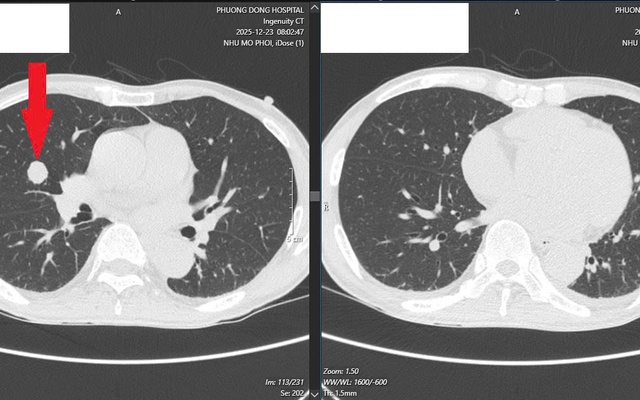

Ung thư lan khắp gan, phổi sau 6 tháng uống chanh muối để tự “chữa lành”

Sống khỏe 2026-01-10T13:00:00Rơi vào tuyệt vọng khi biết mình mắc ung thư trực tràng di căn gan, bệnh nhân 68 tuổi đã từ chối điều trị bằng y học hiện đại để về nhà tự “chữa lành”.